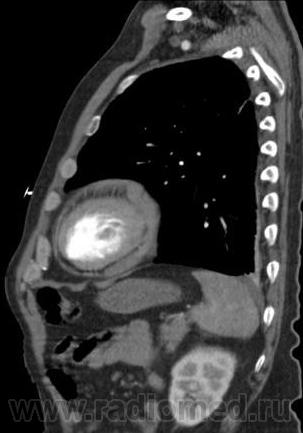

Рассоение аорты тип "A". Восходящий, нисходящий отдел, дуга, переход на брахиоцефалы...

Здраствуйте,я новый участник, и только начинающий врач- но у меня уже был один такой случаий- по моему это аневризма аорты с расслоением.Если бы вы прошли до бифуркации аорты -и там тоже увидели аневризму с расслоение то можно было бы поставить диагноз- аневризма с расслоением по Де Бейки- 1 тип.А какая опереция на сердце?

Ага, я видно поторопилась. Когда я писала, были только аксиалы и то не все. Теперь, когда появились фронтальные реконструкции вижу переход на устье плечеголовного ствола. Есть признаки разрыва: жидкость в плевральной полости и немного в легком.

Ну, в данном случае понятно, что просвет который законтрастирован слабее - является ложным. Но в некоторых случаях, довольно сложно определить истинный и ложный просвет. В этом могут помочь: 1. Истинный просвет обычно меньше на аксиалах 2. СимПтом 'клюва' или 'beak sign" - наиболее характерный признак для ложного прросвета ( четко представлен в данном случае)то есть есть клювообразные выпячивания по периферии ложного просета в сторону истинного. 3. Cobweb sign - тоже характерен для ложного просвета ( мелкие 'ниточки' от отслоенной интимы в сторону ложного просвета. Другие признаки менее специфичны Доольно сложно иногда бывает отличить где исинный а где ложный просвет прихронических аневризмах.